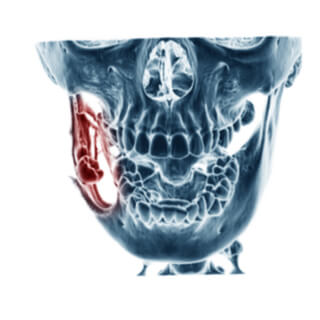

تشخيص سرطان الفك

تتلخّص إجراءات التشخيص فيما يأتي:

• التصوير المقطعي المحوسب.

• الرنين المعناطيسي.

• صورة بانوركس للأشعة السينية.

• الخزعة.